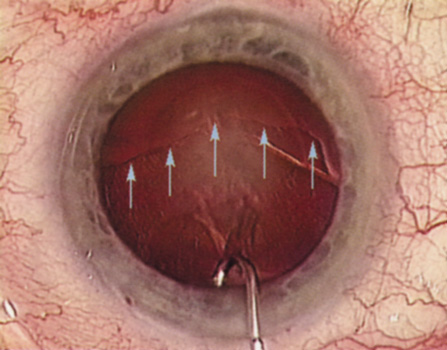

Hydrodissection can be performed after the surgeon has successfully completed capsulorrhexis.97 If the capsulorrhexis is not intact, fluid forced around the interior of the capsule may cause the bag to splay open. With capsulorrhexis, hydrodissection is a safe and extremely useful maneuver. Hydrodissection can be thought of as two maneuvers: hydrodelineation and cortical cleaving hydrodissection. By placing a 27-gauge cannula on a syringe filled with balanced saline solution (BSS), the surgeon can direct fluid beneath the residual anterior capsular rim to create a cleavage plane. Depending on the direction the fluid wave takes, different lamellae of the cataract will be separated. Hydrodelineation is the term used when the cleavage plane separates the adult nucleus from the fetal nucleus or the adult nucleus from the more peripheral epinucleus. Hydrodelineation often results in the characteristic golden ring sign (Fig. 11). Cortical cleavage occurs when the cortex is separated from the capsular bag (Fig. 12). Finding the cortical cleavage plane may be facilitated by gently lifting the capsular margin away from the cortex with the BSS cannula before injecting. Several small bursts of fluid allow the surgeon to monitor progress of the fluid wave. When dealing with a soft nucleus, the authors strive to perform true cortical cleaving hydrodissection. For a hard nucleus, hydrodelineation allows manipulation of less of the nuclear bulk, although the remaining epinuclear shell must be addressed in an additional step. Hydrodelineation is particularly useful if the nucleus is not freely mobile after cortical cleaving hydrodissection.

Fig. 12. Hydrodissection, performed subincisionally with a 27-gauge J-cannula, produces a cleavage plane between the capsule and the cortex. The small blue arrows indicate the advancing fluid wave.